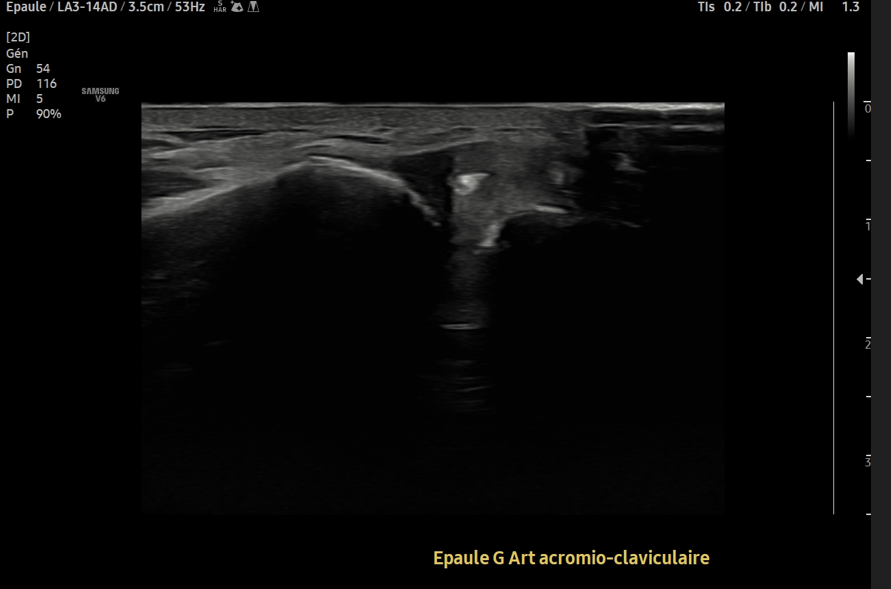

@DrJN_SportsMed L5/S1 discopathy with modic changes and disc bulging ?